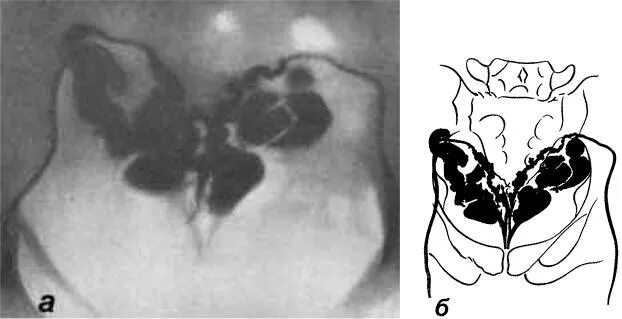

Простатит везикулит